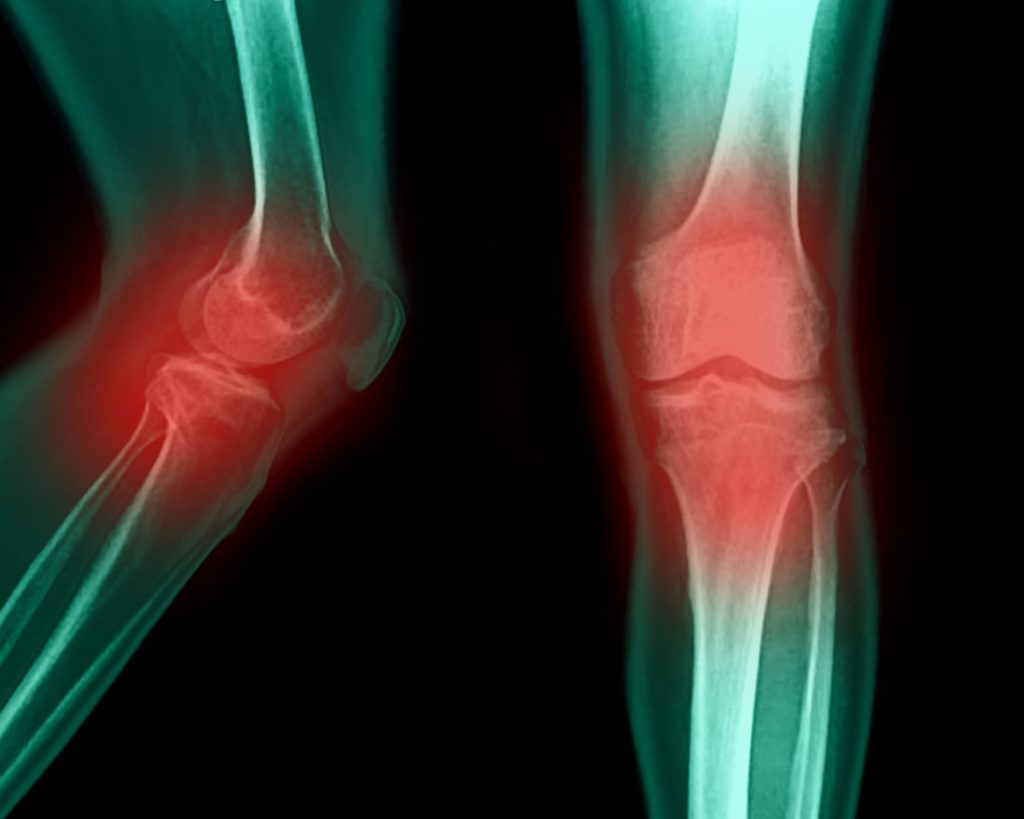

Рентгеновские снимки двух колен, одного сбоку и одного спереди, с красными отметинами, выделяющими суставы.